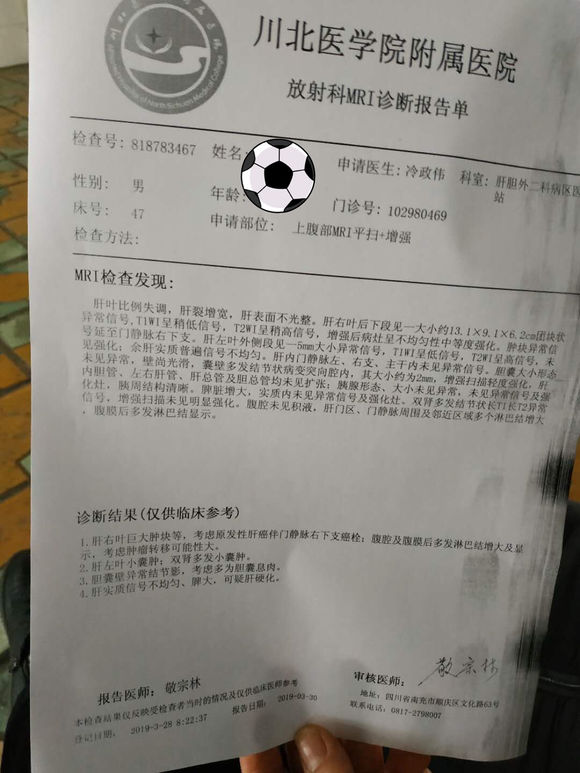

@now 02019-04-12 患者家属昨天查出肝癌。这么办接下来的路这么走?医生说癌细胞转移到胃了。现在吃东西都胃堵住了感觉,不舒服。做磁共振动的时候看电...

超 02019-04-08 患者家属今天是知道爸爸患病的第十三天,当地医院未能确诊转到市医院后医生看了片子得出结论9成以上肝癌晚期。当听到这个消息整个人...